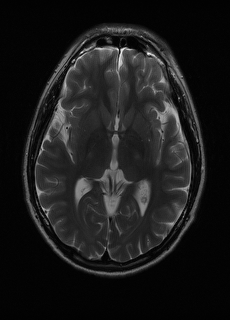

We employ two datasets. The first one is a privately collected, k-space raw data of three sequences (T1subscript𝑇1T_{1}, T2subscript𝑇2T_{2}, FLAIR) from 20 patients, with each sequence containing 18 slices. The sequences are co-registered and taken with an MRI machine with 8 channels; in order to augment training, we treat each channel as an individual image to result in a total of 2,880 three-sequence images, which are divided into a ratio of 17:1:2 for training, validation, and testing. We refer to this dataset as “real data”. In order to further validate our research, we also employ the Brain Tumor Image Segmentation (BraTS) dataset [15, 16], which contains T1subscript𝑇1T_{1}, T2subscript𝑇2T_{2}, and FLAIR. The sequence are co-registered to the same anatomical template, skull-stripped, and interpolated to the same resolution. We divide the selected 167 cases into a ratio of 140:10:17 for training, validation, and testing. From every case, we select the middle 60 slices that contain most of the anatomical details. Because BraTS does not provide raw k-space data, we follow common practices [12, 9] to simulate k-space data. We refer to this dataset as “simulated data”. Below, our insights are first demonstrated with experiments on real data and are further validated on simulated data.

We experiment on both low-pass sampling [12] and random sampling [9]. We found that random sampling works better on real data but worse on simulated data. As our approach is agnostic of sampling strategy, we choose the better performing sampling strategy for each dataset. During BRM training, the masks 1:Ssubscript:1𝑆\mathcal{M}_{1:S} are generated based on a random λs[1,k]subscript𝜆𝑠1𝑘\lambda_{s}\in[1,k], where k𝑘k is the maximum undersampling factor (we set k=8𝑘8k=8). This means that BRM, after training, can handle a continuous set of undersampling factors on every sequence.